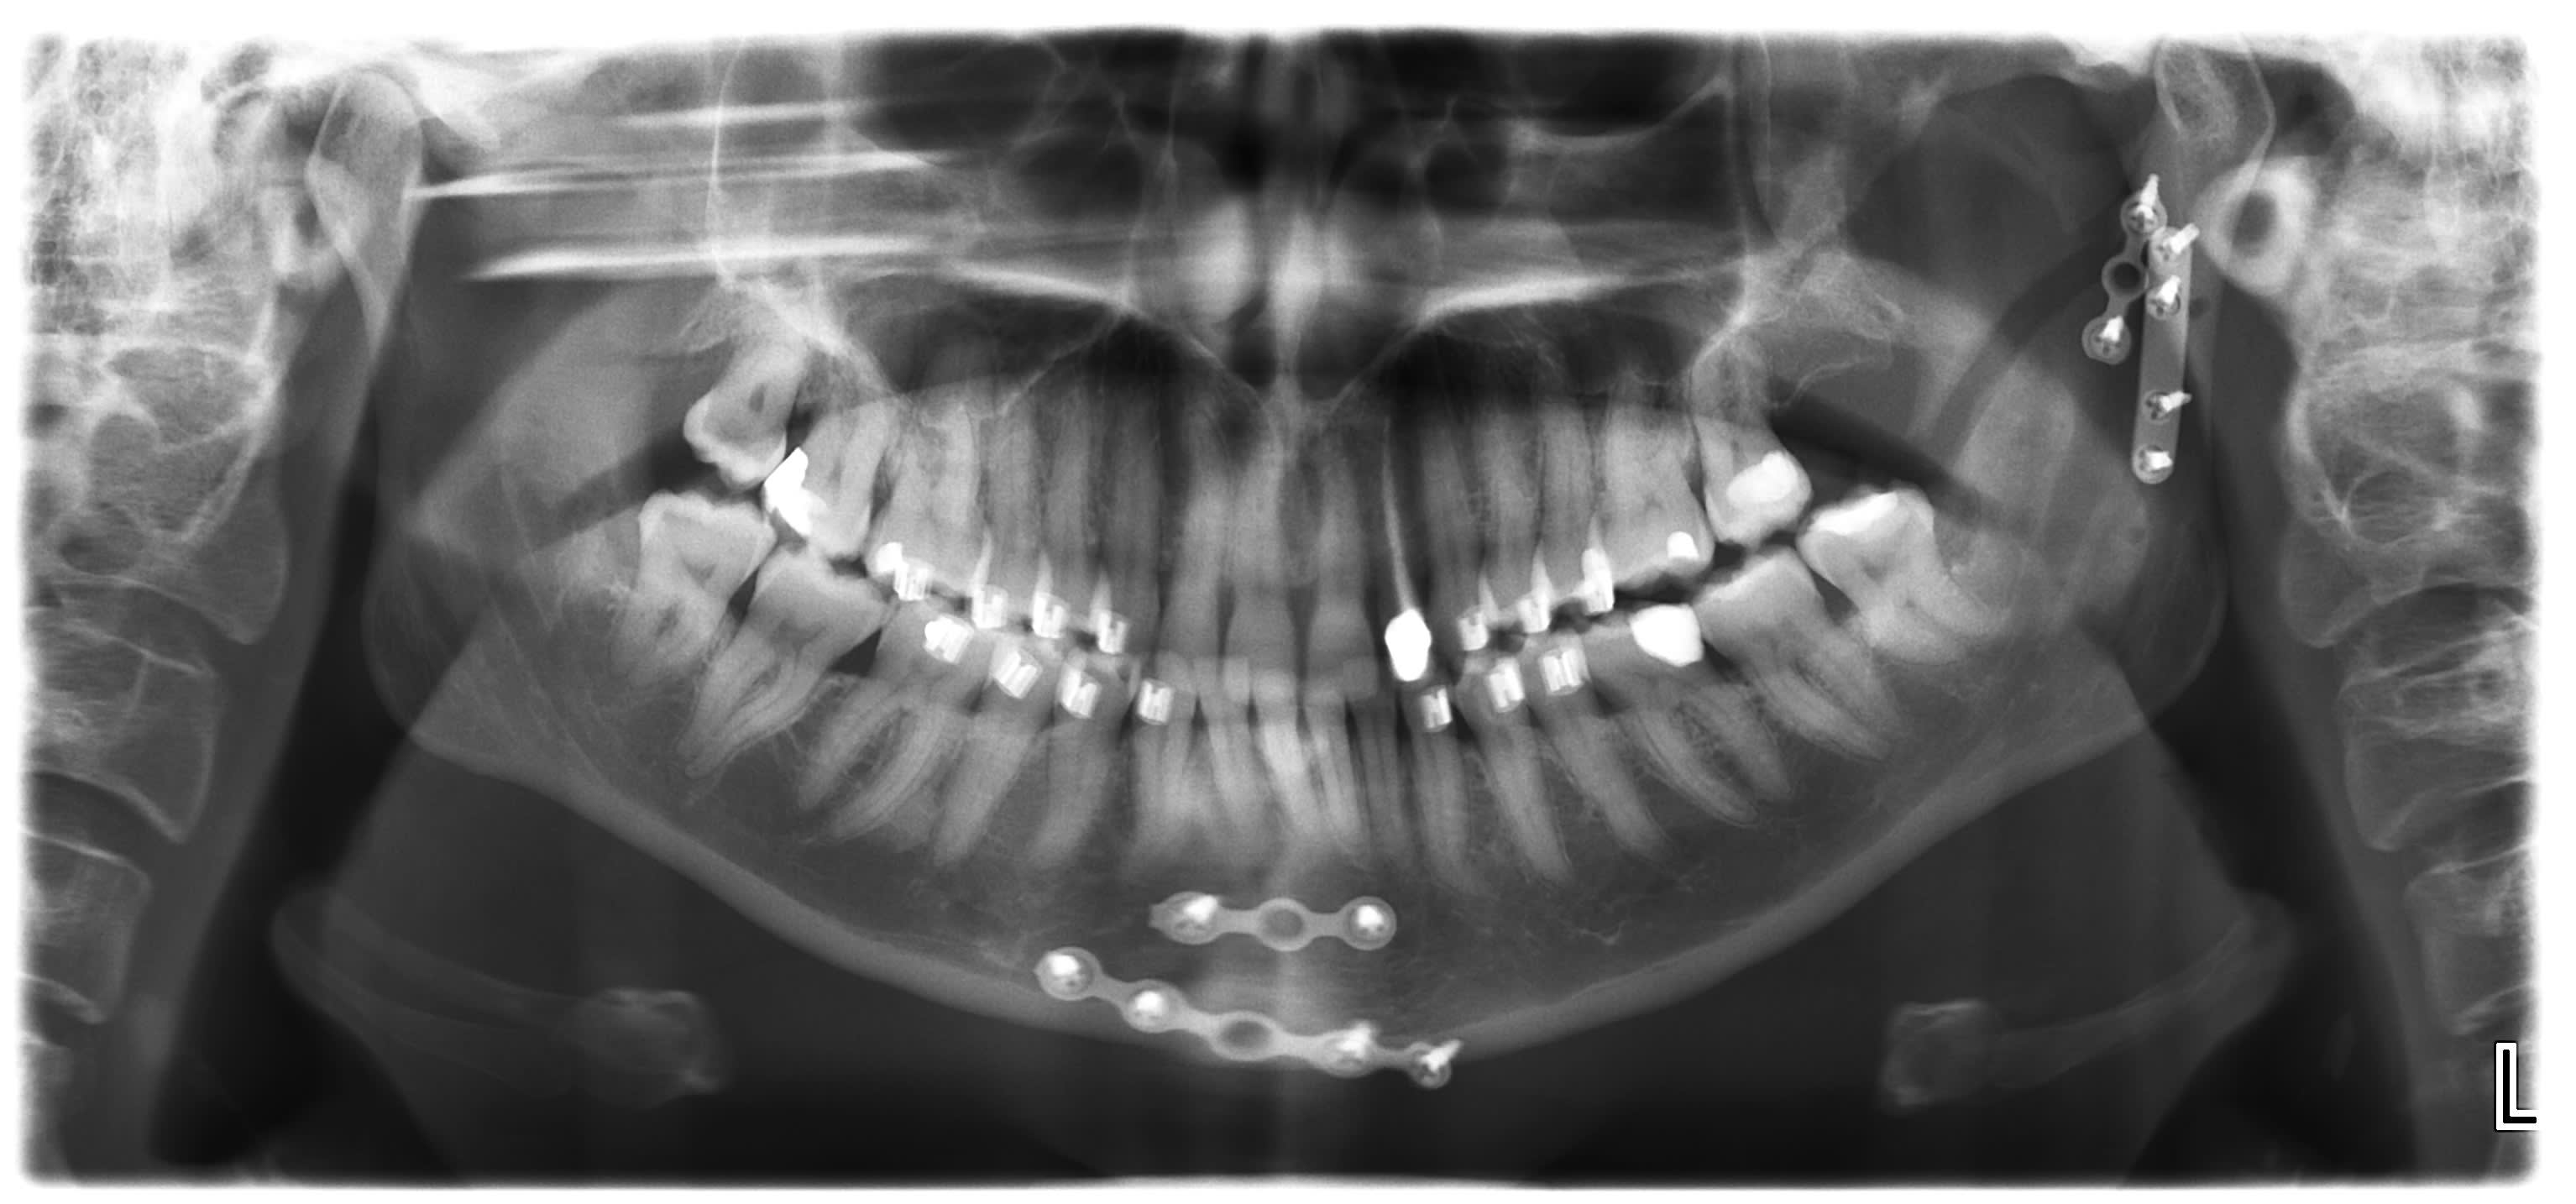

Urgence typique du vendredi, juste avant le wk. Sabot cheval qui a fracture le condyle gauche et symphyse mandibulaire.

Rapide IMF avec brackets, et operation le lendemain. 4 plaques, 2 au condyle et 2 a la symphyse.

Radio controle vendredi..

Trait fracture symphysaire passe au niveau alveole de 41/42.. Ca sent bridge colle.. Wait and see

elastiques 3 semaines. Patiente presque plus de douleurs... Bonne cicatrisation intra et extra orale. Esperons coronoide se remette en place par tensions musculaires.

Peut on esperer une cicatrisation osseuse du coronoide avec un deplacement auusi important ?

Ps : carie sur 18 ;-)